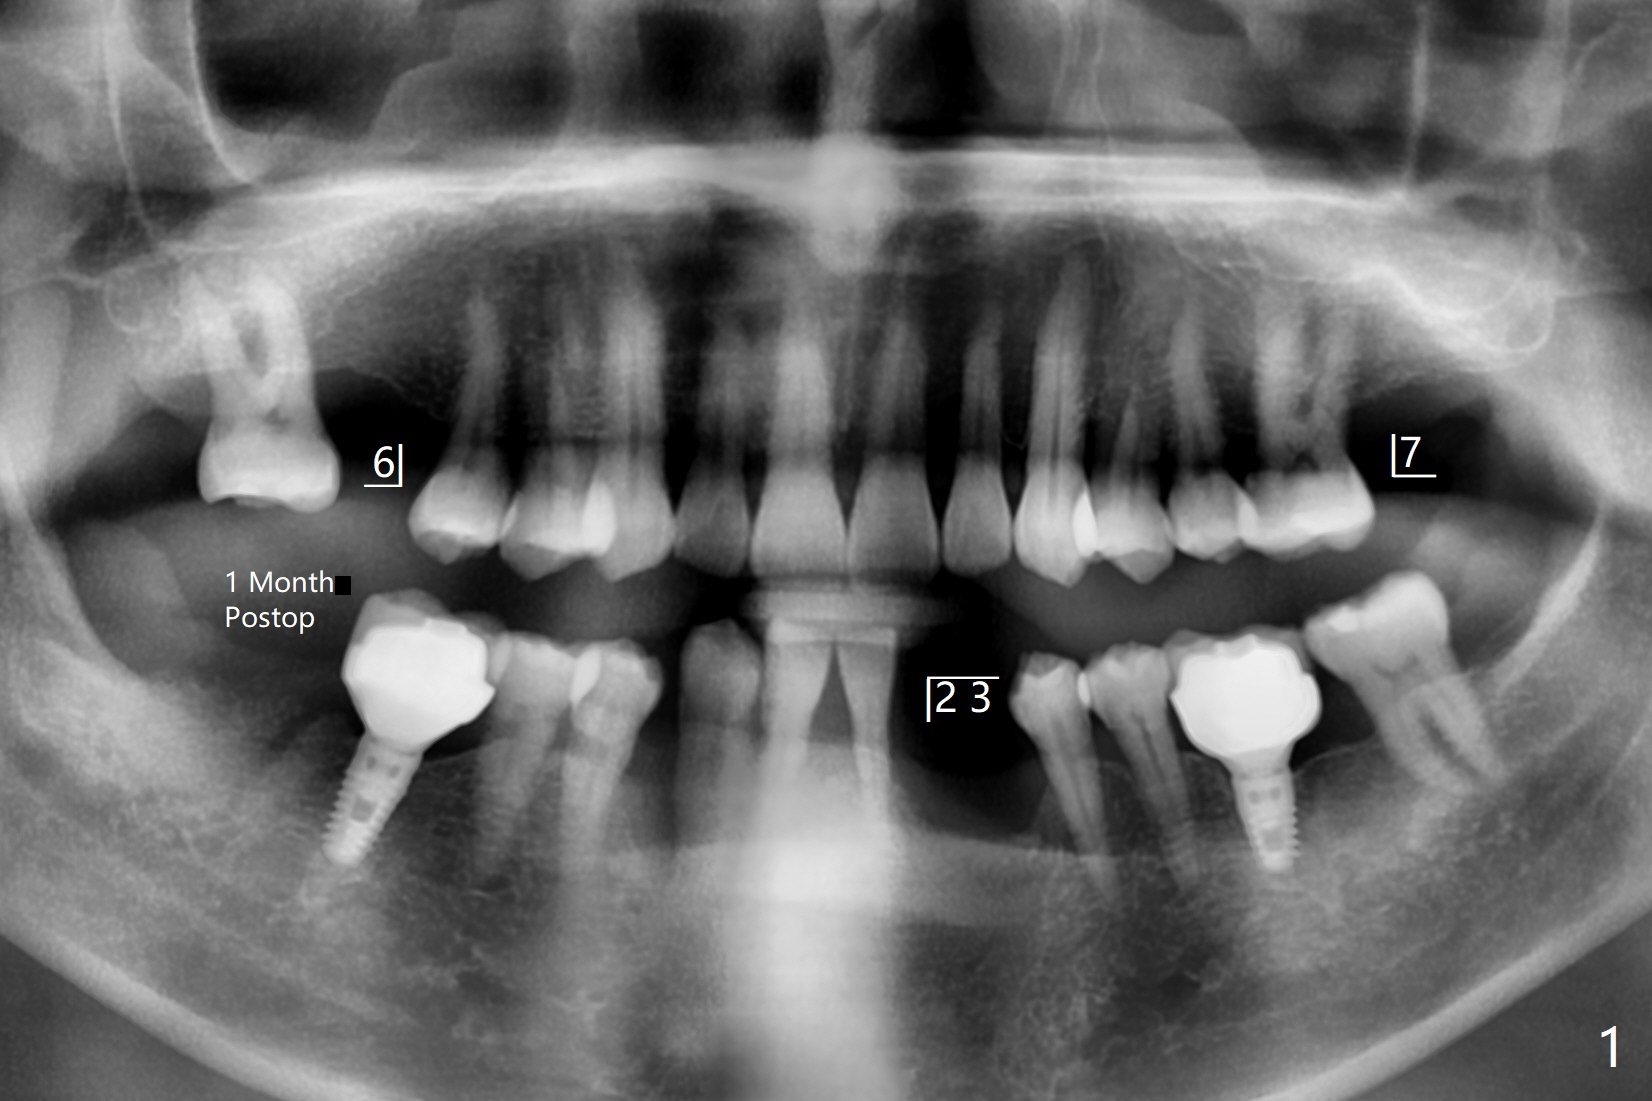

56岁男右下7位点保存一个月,还缺失4个牙齿(图一),左下2,3牙槽嵴特别狭窄,骨皮质为主(图二),应该植入2.0,2.5毫米植体(图三,四),避免复杂植骨术。而右上3骨质也狭窄,但是骨质密度低,几乎松质骨(图五),如果采纳骨膨胀术(高速倒转),植体可以大于4.0毫米,防止植体断裂。左上7骨质宽,但是短,5x8.5毫米植体可能胜任功能(图六)。如果植入10毫米植体,需要做上颌窦提升。